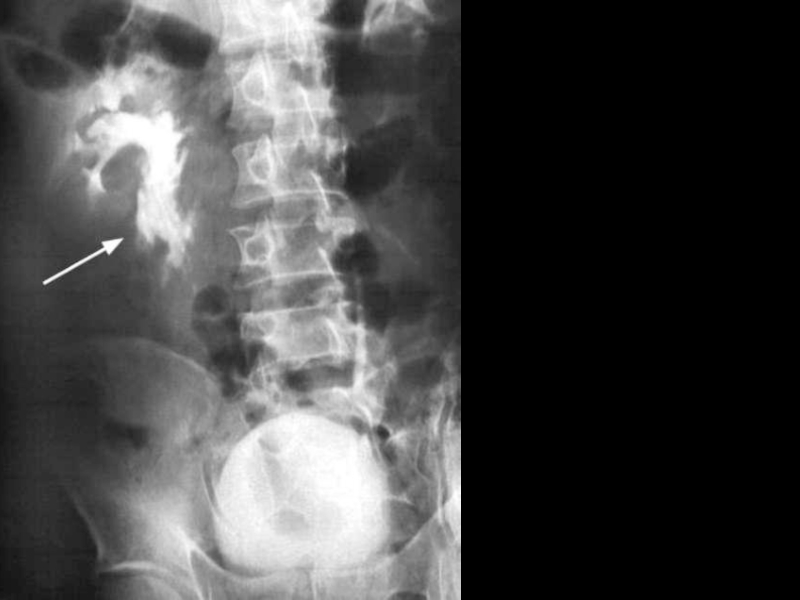

Слайд 11Контрастная ренгенография

Контрастная ренгенография